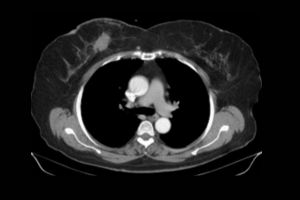

Are you looking for an affordable NCCT Right Leg scan? At Medifyhome, we offer competitively priced MRI and CT scans, partnering with top NABL-certified diagnostic centres and clinics. Our facilities ensure high-quality imaging and accurate results. An NCCT (non-contrast computed tomography) scan of the right leg is a diagnostic imaging procedure that provides detailed cross-sectional images of the bones and soft tissues of the leg without using contrast agents. This scan is commonly utilized to evaluate fractures, bone tumours, infections, and conditions affecting the vascular system. During the procedure, the patient lies still while the CT machine captures multiple images from different angles. The resulting high-resolution images help healthcare providers assess the integrity of the leg’s bones and surrounding tissues. The NCCT scan is quick, safe, and ideal for patients who may have allergies to contrast materials or need urgent evaluations. To book an appointment for an NCCT Right Leg scan, visit our platform, Medifyhome, or contact us at +919100907036 or +919100907622 for reasonable prices.

An NCCT (non-contrast computed tomography) scan of the right leg is a diagnostic imaging test that produces detailed cross-sectional images of the bones, soft tissues, and structures of the right leg without the use of contrast agents. This scan is used to evaluate various conditions, including fractures, bone tumours, infections, and vascular issues. It offers high-resolution images that help healthcare providers accurately diagnose and assess the extent of any problems affecting the leg. The procedure is quick and generally safe, making it suitable for patients who may be allergic to contrast materials or require immediate evaluation. Overall, the NCCT scan is a valuable tool in diagnosing and guiding treatment for leg-related issues.

- The CT machine will rotate around your leg, capturing a series of cross-sectional images from different angles. You may be instructed to hold still and breathe normally, or to hold your breath briefly during some scans.